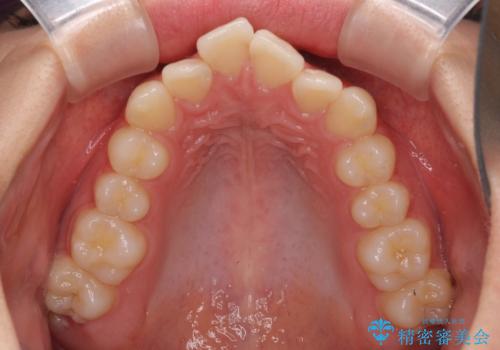

- 口元のデコボコを気にして来院された患者様です。

前歯の捻れにより口元が閉じにくくなっていたため、歯列全体の側方への拡大と、歯と歯の間を少し削ってスペースを獲得することとしました。